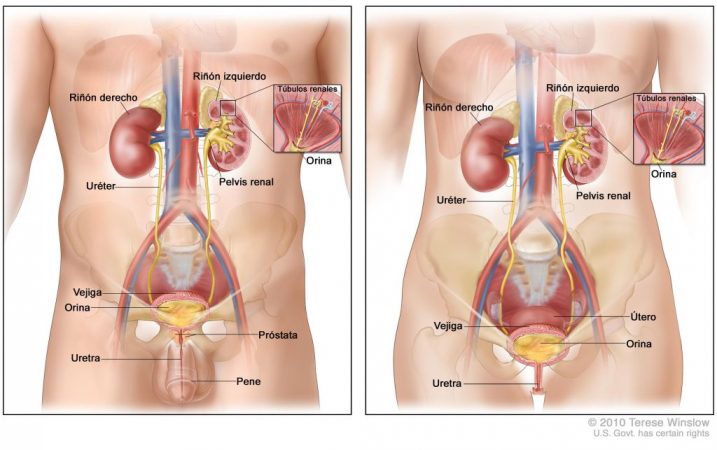

Este cáncer se encuentra en la vejiga, que es el órgano encargado de almacenar la orina en poca presión. Este cáncer se ubica en la mucosa que está en contacto con la orina. Es el décimo cáncer en los hombres y casi el tercero en las mujeres.

Tienes que realizarte un análisis de sangre y uno de orina. En la primera, se ve si la función del riñón está afectada y en la segunda para comprobar las alteraciones, aunque en algunos casos tienes el cáncer, pero la orina da limpia.